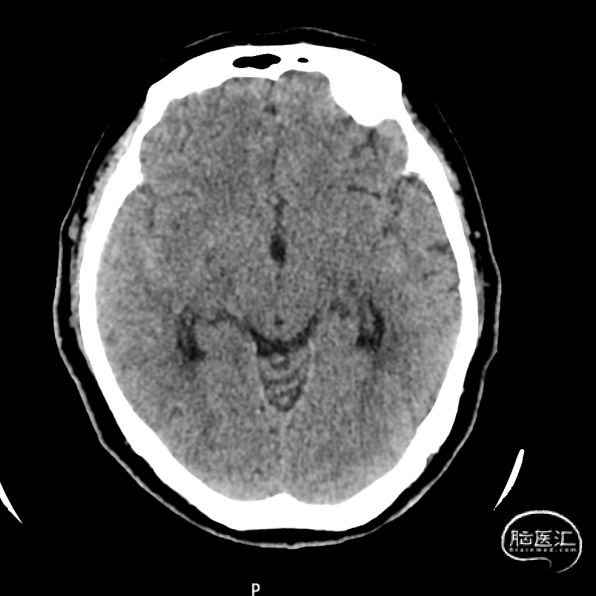

术前CT:双侧外侧裂及部分脑沟内高密度影。右侧桥小脑角区、双侧外侧裂及脑沟内示多发条片状密度增高影,边界欠清。

术后CT。